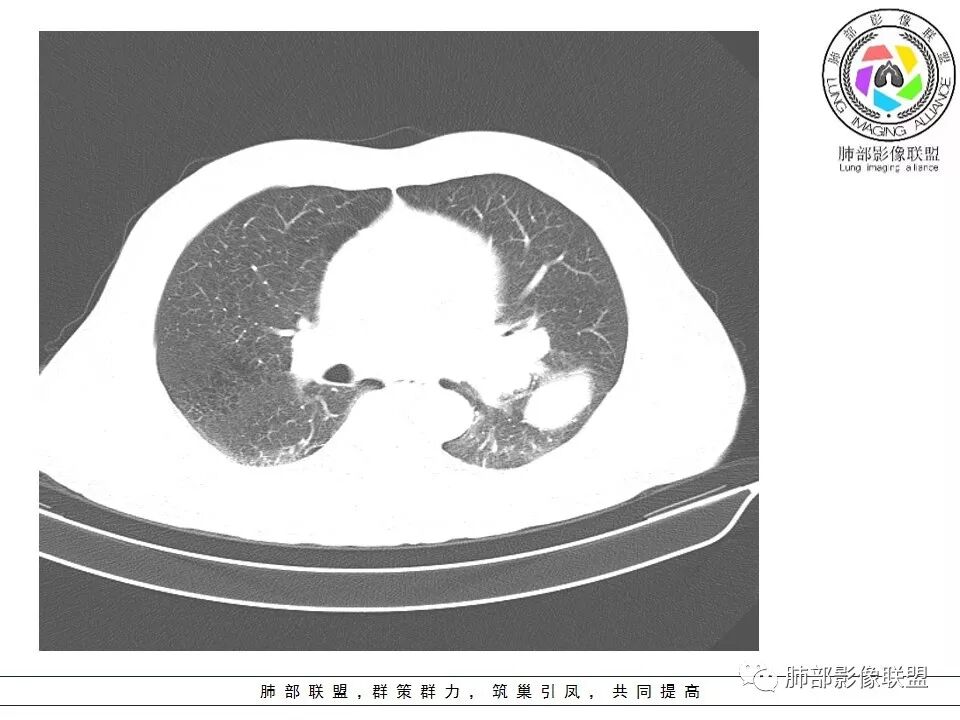

1.左肺下叶近肺门区肿块,肿块外围大,内带小,提示外围向中央生长,符合周围型SCLC沿支气管方向生长。

2.病灶边缘光滑,未见明显分叶、毛刺,符合神经内分泌癌、癌肉瘤及间叶来源肿瘤。

3.病灶内密度偏低,穿行血管未见明显异常,轻度不均匀强化,为乏血供病灶。病灶内可疑坏死区,未见空洞;乏血供符合SCLC,但坏死区不符合。

4.病灶区支气管以受压推移为主,管腔不规则,腔内通而不畅,提示病灶粘膜下为主,符合SCLC迁徙蔓延或间叶来源肿瘤。

7.未见明显阻塞性炎症及阻塞性肺不张,更加提示病灶从外围向中央侵犯,符合SCLC罕见阻塞性肺不张。

阻塞性炎症轻,阻塞性肺不张少见

支气管内肿瘤大多来自淋巴结转移,而且侵入支气管管壁的SCLC组织喜欢沿粘膜下组织间隙浸润,支气管粘膜面保留,所以支气管大多数表现为狭长而非填塞或截断,所以阻塞性炎症轻,阻塞性肺不张罕见。

6边缘圆钝、光整,未见毛刺

神经内分泌肿瘤边缘通常圆润,而且SCLC或周围没有任何促纤维结缔组织反应,质地软,所以边缘圆钝、没有毛刺。